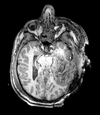

Slicer Registration Library Case 38: TBI

| T1pre | FLAIR | T1post | coronal T2 | SWI | EP50 | EP75 | EP100 |